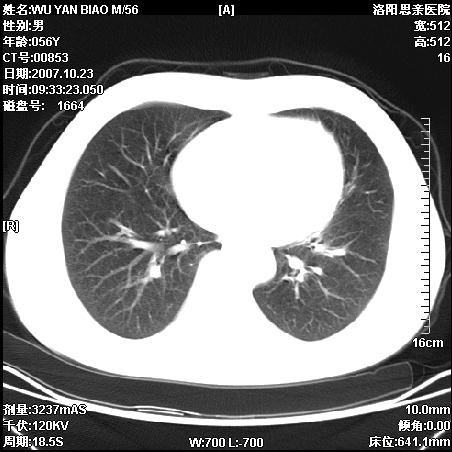

标题: CT10160:M56Y,体检发现,病人无不适,病人随访中 [打印本页]

标题: CT10160:M56Y,体检发现,病人无不适,病人随访中

后上纵隔占位,与肺交界清,宽基底附着脊柱,密度均匀,局部骨质无明确改变.

考虑;神经源性肿瘤,---起源交感n链?,不除外肠源性囊肿.

1、病灶在后纵隔脊柱旁沟内,此处是神经原性肿瘤的好发部位

2、病灶边缘光滑整齐,更说明病灶来于纵隔,由于有胸膜的包裹所以才导致这么光滑的边缘

3、病灶内的密度均匀